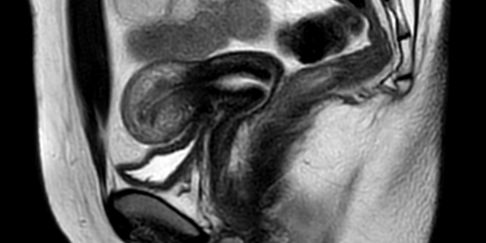

L’esame RM della pelvi femminile è un esame che viene svolto con relativa frequenza negli studi di risonanza magnetica.

Le motivazioni per cui viene eseguito questo esame sono le più disparate sicuramente la frequenza più elevata e relativa alle patologie espansive o tutte quelle che sono le lesioni di tipo indeterminato po’ sospetto all’esame clinico ecografico. Viene spesso seguito anche nei contesti di dolori pelvici, dolore durante le mestruazioni e dolori durante rapporto sessuale. Non mancano ovviamente i casi in cui viene eseguito per dolori generici che non sono però specifici o caratteristici dell’endometriosi.

Un altro quesito diagnostico solitamente può essere quello della valutazione di lesioni espansive conosciute e già diagnosticata da un punto di vista istologico e che vanno quindi valutate a livello locoregionale e linfonodale per quanto riguarda la presa in carico a livello del trattamento. Un’altra motivazione può essere sicuramente quella del controllo a distanza di lesioni già studiate e che non sono state considerate come sospette per poi non procedere come eventuali indagini ma semplicemente ritardare il controllo successivo eri valutarle con una nuova risonanza magnetica a distanza di 6 12 mesi da quel punto eventualmente prendere una decisione più concreta se eventualmente interrompere il follow up diagnostico può passare ad una diagnostica più invasiva e istologica. Nella descrizione generica che vorrei dare dei protocolli di studio RM della pelvi femminile ovviamente escludo tutte quelle che sono le patologie che erano riguardano nello specifico l’apparato genitale femminile quindi intendo tutte le patologie che riguardano anche i pazienti maschi, ad esempio le fistole anali, le patologie dell’ano, la patologia vescicale e le patologie dell’ultimo tratto intestinale. Osservando quelli che sono i differenti protocolli di studio delle patologie della RM femminile pelvica possiamo osservare che sostanzialmente hanno tutti la stessa struttura e differiscono solo eventualmente dall’utilizzo o meno della saturazione del grasso in T2 in uno dei piani oppure sono caratterizzati dall’utilizzo o meno del mezzo di contrasto. A tal proposito in alcuni casi si può vedere come sia estremamente utile lo studio dinamico durante somministrazione di mezzo di contrasto in particolare per quello che riguarda i determinate lesioni ovariche e soprattutto lo studio delle lesioni sospette dell’endometrio.